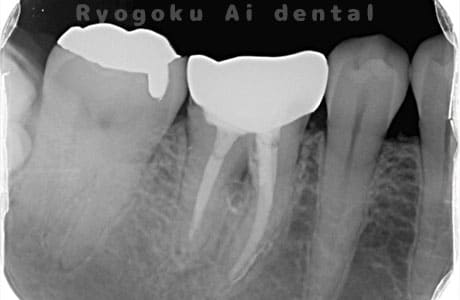

Case05

-

術後2ヶ月

- 原因

- 右下6番近心根パーフォーレーション

- 治療内容

- 外科的パーフォレーションリカバリー治療

- 治療費用

- ¥66,000

右下の奥から2番目の歯に穴が空いており、腫れが引かず、他院で抜歯と診断された患者様です。被せ物を外さずに、穴が空いている部分に外科的にアクセスし、その部分を修復手術を行いました。治療後も再発せず、経過良好です。

<リスク・副作用>

手術後は痛み、腫れ、痺れ、青あざなどの副作用が生じます。痛みは痛み止めを処方しますが、腫れ、青あざは1週間程度生じる場合があります。また、部位によっては神経の走行が複雑で、痺れが残り、長期的にお薬を処方する場合があります。